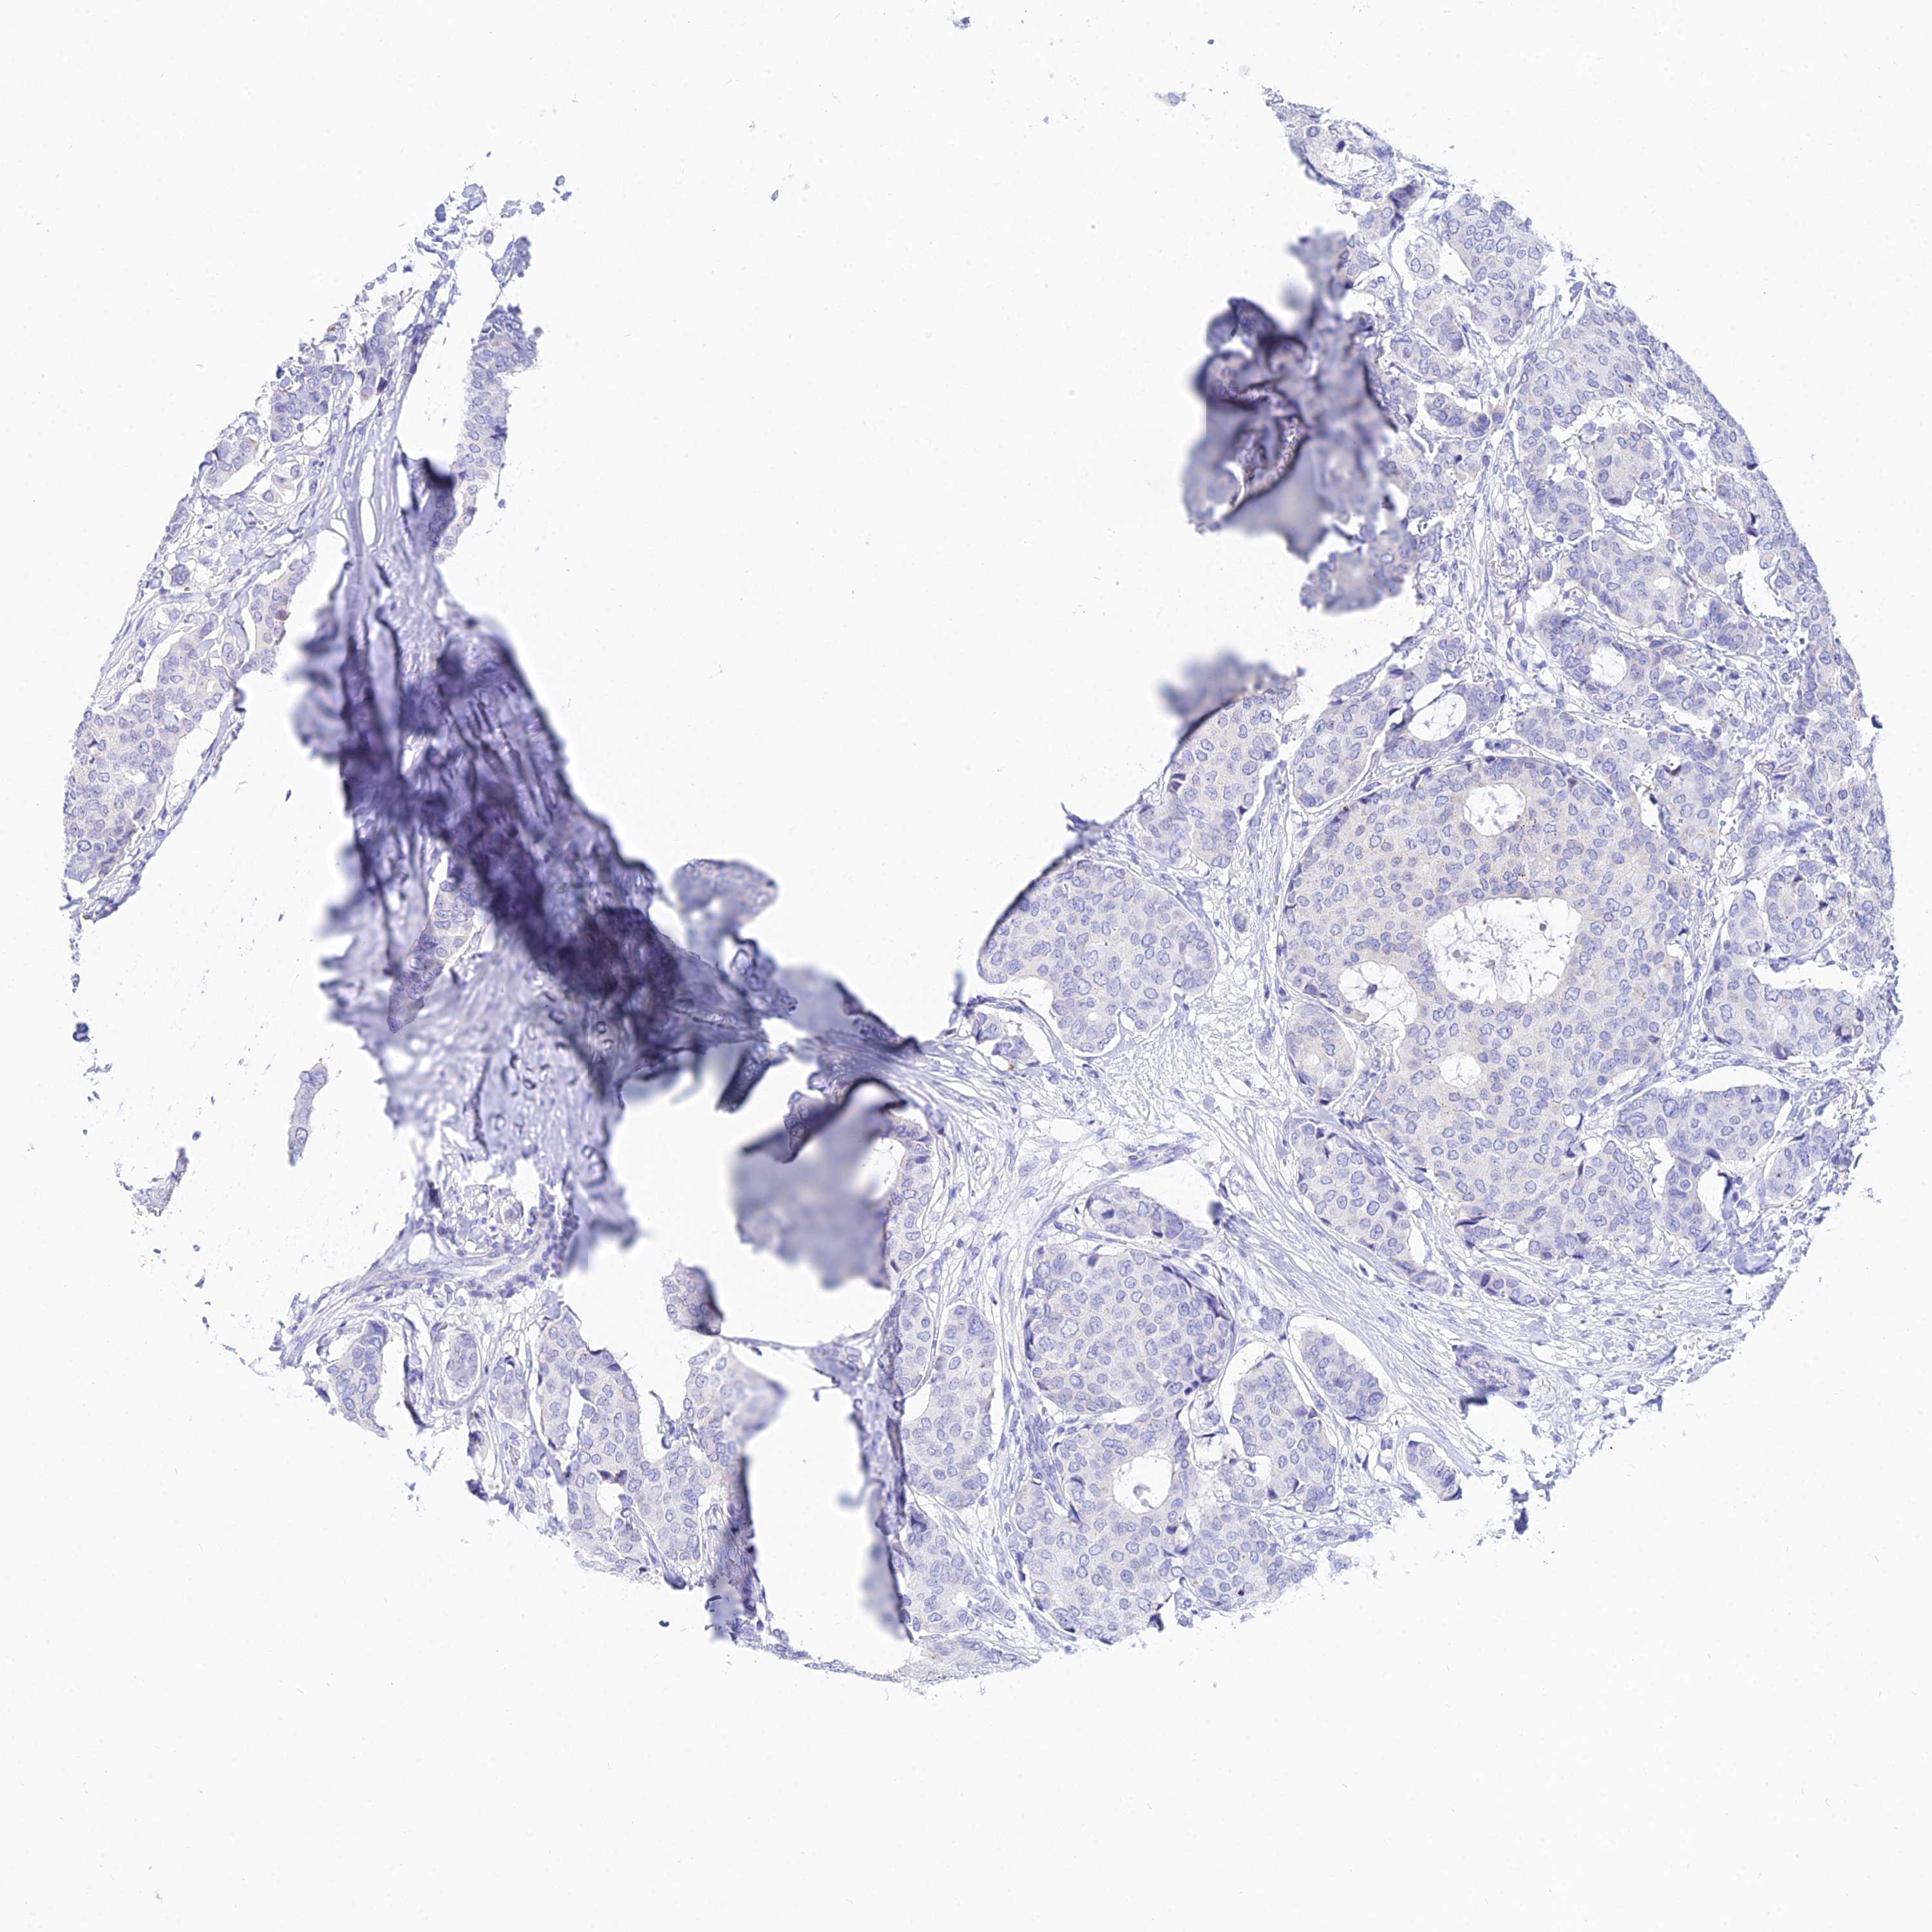

CANCER BREAST CANCER Show tissue menu

BRCA TCGA BRCA VALIDATION PROTEIN EXPRESSION

Breast cancer

Human cancer